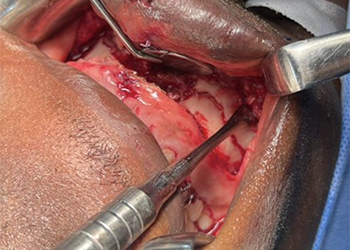

Las vistas intraoperatorias mostraron una reducción precisa de los segmentos de fractura, y el equipo quirúrgico realizó un reposicionamiento anatómico y una fijación interna rígida, asegurando una alineación adecuada de los contrafuertes faciales. Las placas maxilofaciales se moldearon para adaptarse a la curvatura facial natural del paciente, mejorando la estabilidad de la fijación.